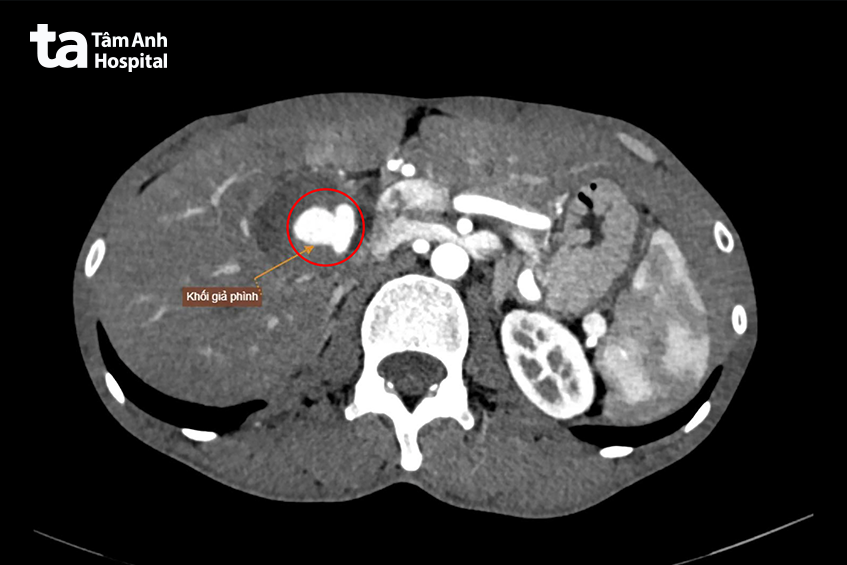

Để tìm nguyên nhân, người bệnh được chỉ định chụp cắt lớp vi tính (CT Scan) ổ bụng có tiêm thuốc cản quang. Kết quả hình ảnh cho thấy một tình trạng hiếm gặp và đặc biệt nguy hiểm là nhiều túi giả phình mạch máu nằm rải rác trong ổ bụng, xuất hiện ở hàng loạt vị trí quan trọng như động mạch gan, vùng dạ dày, thận và vùng thắt lưng.

Đáng lo ngại nhất là khối giả phình lớn nằm ngay vùng rốn gan, xuất phát từ nhánh động mạch gan phải. Khối này có kích thước lên tới 40 x 40 x 65 mm, tương đương một quả trứng nhỏ, chèn ép các cấu trúc xung quanh, làm rối loạn tưới máu nhu mô gan và đè ép tĩnh mạch thận phải. Nguy hiểm hơn, khối giả phình đã vỡ, gây tụ máu xung quanh, tiềm ẩn nguy cơ xuất huyết ồ ạt trong ổ bụng nếu không được xử trí kịp thời.